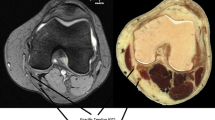

The QPA graft harvest and reconstruction has been described in detail [7]. In short, a 1 cm wide by 1.5 cm long by 1 cm deep trapezoidal bone block is cut from the patella and removed with a curved 3/8th inch osteotome. As the bone block is excised and elevated, a 10-mm-wide central section of the quadriceps tendon is separated from the remaining quadriceps fibers until the entire graft reaches 65 mm in length including the bone block. The graft is prepared, and the diameters of the soft-tissue and the bone-block ends are each measured to the nearest 0.5 mm. The intraoperative graft diameter measurements were completed with a sizing block and recorded as the smallest hole each end of the graft could fit through. Of note, the bone-end side of the graft was measured at the soft tissue immediately proximal to the bone block. The soft tissue diameter immediately proximal to the bone block does necessarily match the size of the bone block for each patient. After graft preparation, the patellar-bone block is seated into the femoral tunnel and the soft-tissue end is seated into the tibial tunnel.

The correlation between the bone-end graft diameter and the MRI AP measure (mm) of the quadriceps at 10 mm above patella was weak and non-significant (Fig. 2; rs = − 0.03; p = 0.76). The MRI diameter significantly underestimated bone-end graft diameter (7.3 ± 1.1 mm vs. 10.6 ± 0.3 mm; p < 0.001). The correlation between the soft-tissue side graft diameter and the MRI-predicted graft diameter at the most proximal available measurement above the patella was strong and significant (Fig. 3; rs = 0.51; p < 0.001). As with the bone-end, however, the MRI measurement significantly underestimated the harvested soft-tissue graft diameter (7.4 ± 1.1 vs. 9.6 ± 0.8; p < 0.001).

On the bone-end of the graft, the difference between the harvested graft diameter and MRI measurement was 3.3 ± 1.2 mm, while the difference on the soft-tissue end was 2.2 ± 1.0 mm. Defining an accurate MRI measurement as within 1 mm of the true graft size, the MRI was accurate 5% of the time on the bone-end, and 11% of the time on the soft-tissue end.